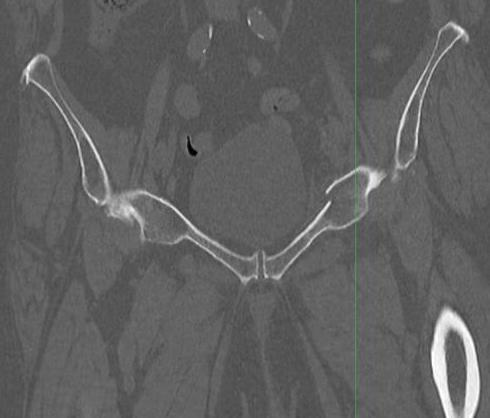

Rommens and Hofmann Classification (CT)

Type I: Anterior pelvic ring only (17.5%)

Type II: Non displaced posterior pelvic ring (50%)

Type III: Displaced unilateral posterior pelvic ring (10%)

Type IV: Displaced bilateral posterior pelvic ring (20%)